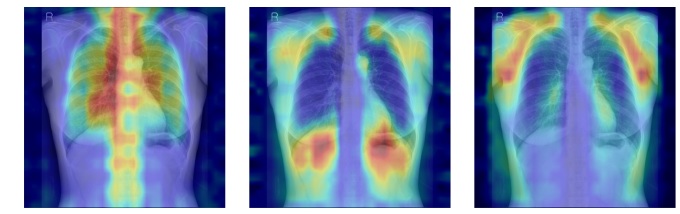

뼈를 모두 가린 상태에서 특정 뼈 부위를 추가해 성능이 얼마나 향상하는지 확인하는 '차단 분석 방식(Δbone)'과 Grad-CAM(딥러닝 모델을 시각적으로 설명해주는 기법)으로 나타난 AI의 주목 영역이 실제 뼈 위치와 얼마나 일치하는지를 계산하는 '유의성 지도 방식(IoUbone)'을 통해, AI가 임상적으로 중요한 뼈 구조를 근거로 판단하는지를 정량적으로 검증했다.

그 결과, DINOv2 모델에 LoRA 방식을 적용한 모델이 AUC 0.93(95% CI 0.92–0.94)로 가장 높은 예측 성능을 보였다. 이 모델은 뼈 구조 활용도가 가장 높고, 주목 영역의 타당성에서도 우수해, 예측력과 설명 가능성이 균형 있게 확보된 최적 모델로 평가됐다.